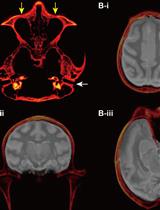

Targeted Delivery of Chemogenetic Adeno-Associated Viral Vectors to Cortical Sulcus Regions in Macaque Monkeys by Handheld Injections

KO Kei Oyama

YN Yuji Nagai

TM Takafumi Minamimoto

1695 Views

Dec 5, 2023

Recent advancements in chemogenetic tools, such as designer receptors exclusively activated by designer drugs (DREADDs), allow the simultaneous manipulation of activity over a specific, broad brain region in nonhuman primates. However, the introduction of DREADDs into large and complexly shaped cortical sulcus regions of macaque monkeys is technically demanding; previously reported methods are time consuming or do not allow the spatial range of expression to be controlled. In the present report, we describe the procedure for an adeno-associated viral vector (AAV2.1) delivery via handheld injections into the dorsolateral prefrontal cortex (Brodmann’s area 9/46) of macaque monkeys, with reference to pre-scanned anatomical magnetic resonance images. This procedure allows the precise delivery of DREADDs to a specific cortical region.Key features• This article describes the procedures for injecting viral vectors encoding functional proteins for chemogenetic manipulation into targeted cortical sulcus regions.• The protocol requires magnetic resonance imaging for the accurate estimation of the injection sites prior to surgery.• Viral vector solutions are injected using a handheld syringe under microscopic guidance.• This protocol allows for the precise introduction of designer receptors exclusively activated by designer drugs (DREADDs) to large and complex cortical regions.